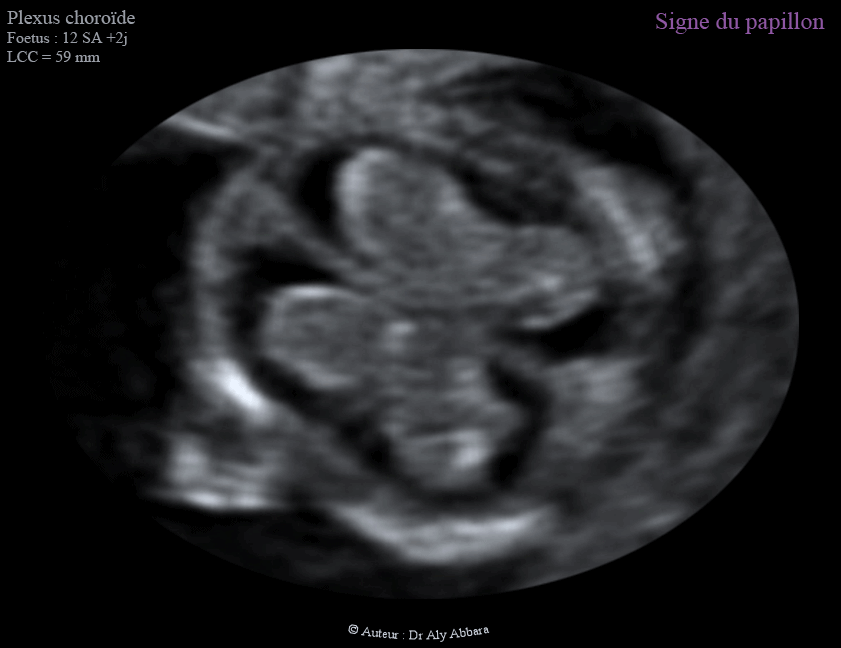

Les plexus choroïdes et le signe du papillon - 12 - 13 SA - الضفائر المشيمية في الدماغ وعلامة الفراشة

Les deux plexus choroïdes et le signe du papillon - 12 - 13 SA - الضفائر المشيمية في الدماغ وعلامة الفراشة

Le signe du papillon

Un signe échographique permettant d'exclure le diagnostic de l'holoprosencéphalie alobaire au cours du premier trimestre de la grossesse :

• Au cours du premier trimestre de la grossesse, entre 11 et 14 SA, les deux plexus choroïdes normaux occupent largement les deux ventricules latéraux et composent ensemble une forme ressemblant à un papillon "signe du papillon - Butterfly sign" ; ce signe est absent dans l'holoprosencéphalie alobaire.

• En cas d'holoprosencéphalie alobaire, on peut observer la présence d'un ventricule unique au lieu des deux ventricules latéraux du cerveau, puis l'apparence anormale des plexus choroïdes : absence du " signe du papillon "